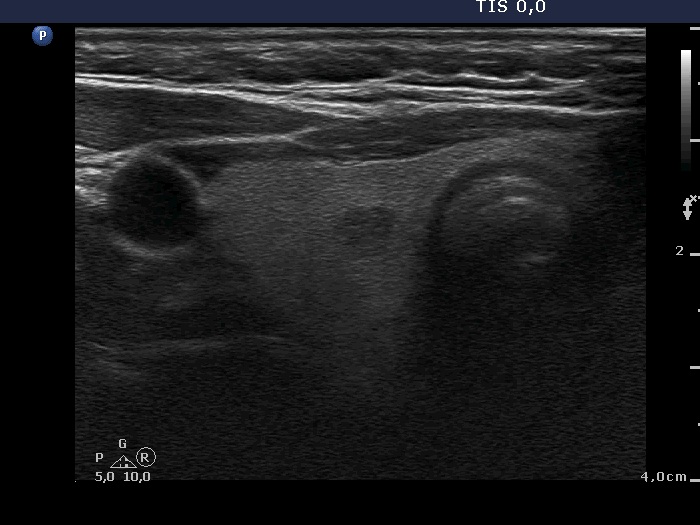

Ultrasonography. The right lobe was echonormal and contained several small, insignificant lesions. There was a hypoechogenic, irregularly shaped mass in the lower half of the left lobe. The lesion had a rigged, echonormal core which showed bright hyperechogenic granules. There were multiple incomplete acoustic shadows dorsal to the lesion which was avascular.